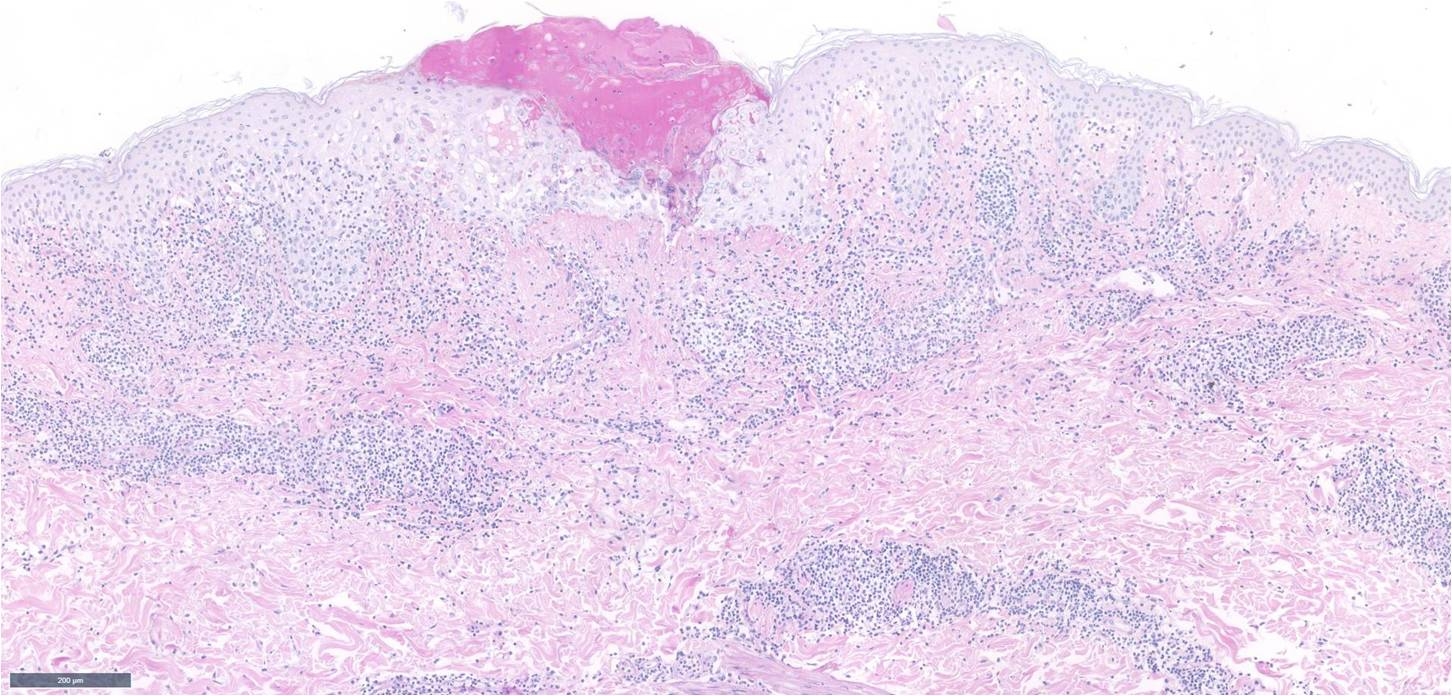

Abdomen 5mm punch biopsy. Active lesion ? papular urticaria